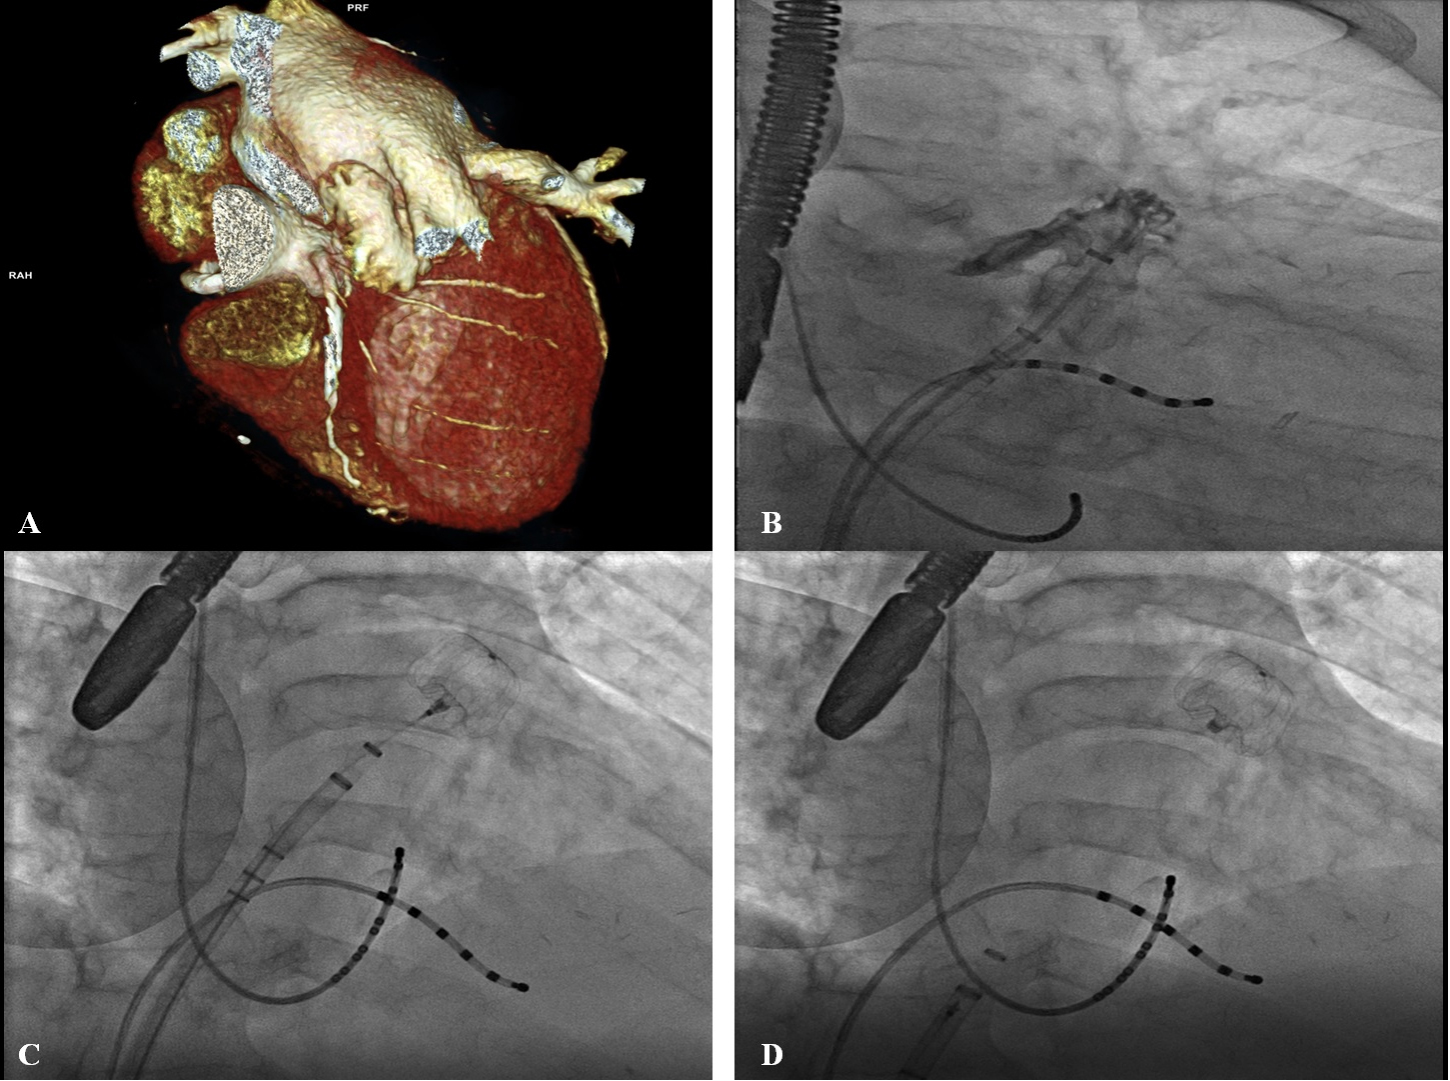

The procedure, typically performed under general anesthesia, should be performed under fluoroscopy and TEE or ICE. The measurement should be confirmed with angiography, and before releasing the device fluoroscopy or TEE should be used to evaluate correct positioning, stability (Tug test), correct size, and proper occlusion. If placement is not satisfactory, the device can be recaptured and repositioned [32] (Fig. 3).

Fig. 3.TEE monitoring during percutaneous LAAO with Lambre device. (A) Highlights device release. (B) Describes in 2 D and 3 D modality TEE the complete occlusion of LAA.